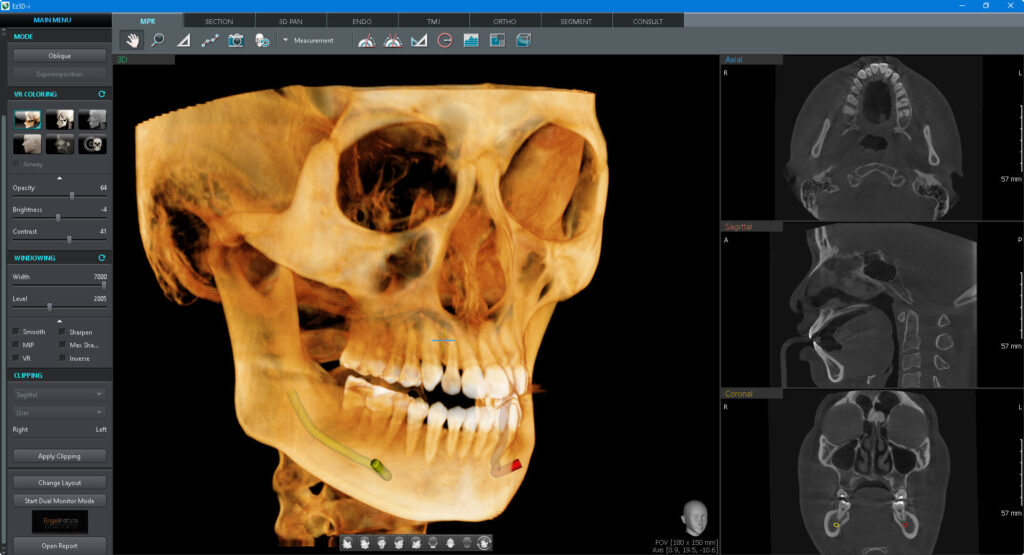

EL SISTEMA MÁS AVANZADO DE RAYOS X DIGITAL 4 EN 1

Green X incorpora pano, ceph (opcional), CBCT y escaneo de modelos.

Proporciona imágenes de alta calidad con menor radiación al combinar el procesamiento de imágenes con la amplia experiencia de Vatech en el campo de las imágenes dentales, mejorando la precisión de tu diagnóstico y una mejor planificación del tratamiento.

IMÁGENES

Tomografía

Panorámica

Lateral de craneo

Bitewing